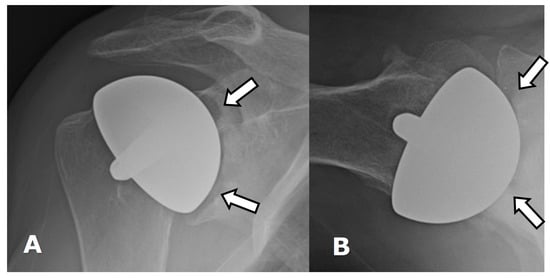

4.2.1. Loosening and Hardware Dissociation

4.2.2. Stress Shielding and Fractures